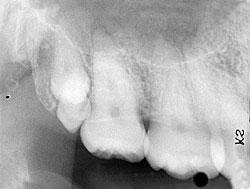

Based on the clinical examination of the patient, selected periapical radiographs and bitewing films were ordered. A review of the periapical films revealed two tooth-like radiopacities in the right maxillary tuberosity area (see radiograph). The location of the radiopacities was distal to the erupted third molar. No other abnormalities were noted on the radiographs.

The distomolar, as the name implies, is located distal to the third molar. It is the second most common supernumerary tooth. This tooth does not interfere with the normal eruption pattern of the first and second molars. The distomolar may resemble a normal molar in size and shape, or may appear rudimentary and miniature. The distomolar may erupt or remain impacted.

Dental radiographs (periapical, bitewing, and panoramic films) can be used to identify unerupted supernumerary teeth. Such teeth can be identified on a radiograph after the ages three or four (primary dentition) and after the ages nine to 12 (permanent dentition). Although the shape and size of supernumerary teeth may vary, the radiographic appearance of the tooth (radiopaque enamel and dentin) is identical to the other teeth on the film.